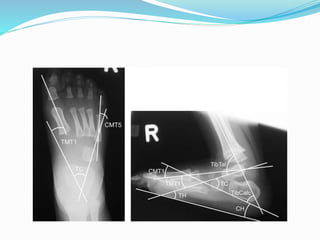

 AP and lateral radiographs of foot in neutral position

 Lateral x-ray in forced dorsi and planti flexion of foot

 Measurements:-on lateral x-ray –

talocalcaneal; tibiocalcaneal, tibiotalar,talar axis 1st

metatarsal base angle(TAMBA)

In CVT-talar axis vertical,calcaneus in equinus and

increased talocalcaneal angle

 Radiological –anteroposterior:

1.talocalcaneal –hindfoot valgus

2.TAMBA-forefoot abduction

lateral:

1.talocalcaneal

2.tibiocalcaneal

3.TAMBA